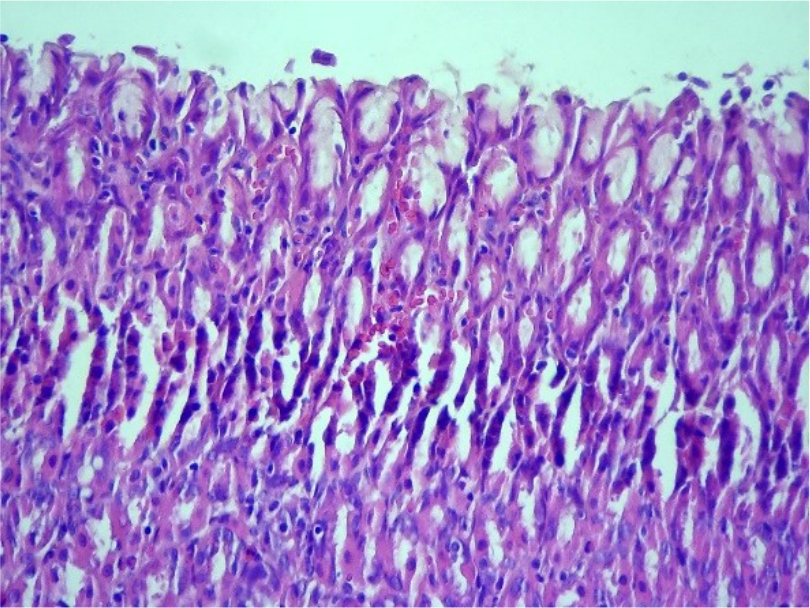

Результаты исследований. При проведении патоморфологического исследования у 10-ти животных из первой группы на 3-й день было выявлено слущивание эпителия слизистой оболочки желудка (Рис.1, 3), расширение просвета желез, очаговая атрофия экзокриноцитов (Рис. 2), на дне желез, часть париетальных экзокриноцитов в состоянии дистрофии с некробиозом – вакуолизацией цитоплазмы, кариопикнозом, границы клеток стерты, гомогенизированы. Васкуляризация стенки желудка активная, крупные сосуды гиперемированы, в подслизистой основе присутствуют единичные эозинофилы.

Рис.1. Слущивание эпителия слизистой оболочки стенки желудка. Ув. ×400

Рис. 2. Атрофия экзокриноцитов желез слизистой оболочки желудка. Ув. ×400